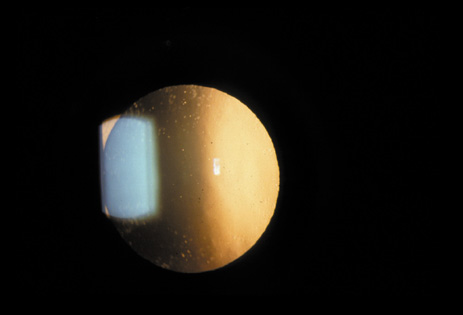

Retrodots are round, translucent opacities that usually occur in the deep cortex or perinuclear region. It has been proposed that they contain calcium oxalate, probably from ascorbic acid.46 In general, they do not seem to affect vision until a mixed cataract appears (nuclear or cortical), and patients may have these retrodots for years and still retain good vision (Fig. 21).

Fig. 21. Retrodots seen on retroillumination examination as refractile bodies. These retrodots are usually seen in nuclear cataracts, are located in the perinuclear or deep cortical areas, and usually do not affect vision.